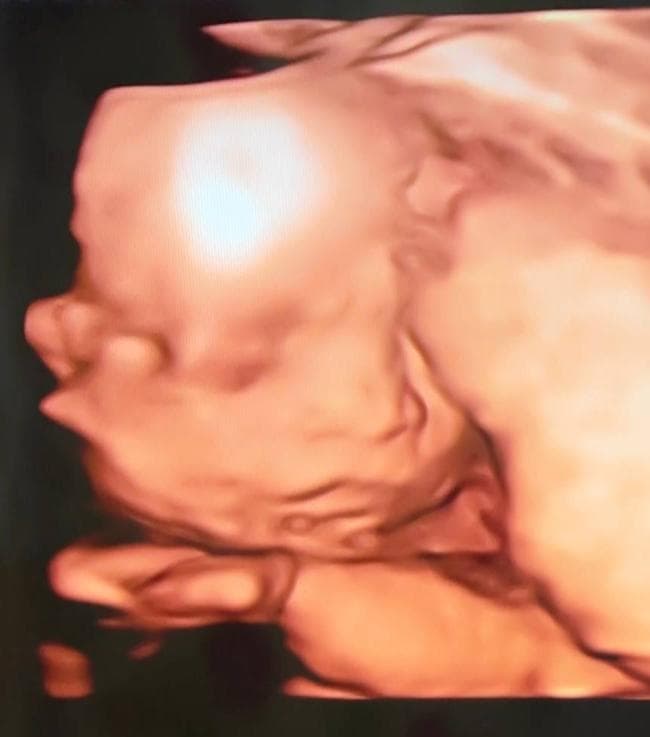

3장 모두 같은 날 촬영한 24주차 딸의 입체 초음파 사진입니다.

• 3번 째 사진

아기 초음파 사진을 보면, 입체 초음파가 태아의 얼굴을 입체적으로 보여주지만, 아직 아기의 얼굴 형태는 많이 변할 수 있습니다. 24주차는 아직 아기의 외형이 성숙해지는 중이고, 얼굴 특징이 점차적으로 달라지기 때문에, 아기마다 얼굴의 비율이나 특징이 조금씩 다를 수 있습니다.

눈사이 거리나 코 크기 등은 아기의 유전자와 성장 단계에 따라 달라지기 때문에, 다른 아기들과 비교했을 때 차이가 있을 수 있습니다. 또한 입체 초음파 사진은 각도나 해상도에 따라 다르게 보일 수 있어, 다른 아기들 사진과 정확하게 비교하는 것은 어려울 수 있습니다.

태아의 얼굴 크기나 특징은 시간이 지나면서 점차 발달하고 성형되는 과정이므로, 걱정할 필요는 없습니다. 담당 의사가 건강 상태를 문제 없이 평가하셨다면, 크게 염려하지 않으셔도 될 듯 합니다. 초음파는 그저 발달 상태를 파악하는 수단일 뿐이니, 아기의 건강이 중요하다는 점을 기억하시고 마음 편하게 기다리세요.